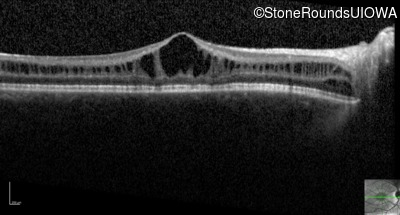

Optical Coherence Tomography - Right - 20/63 -2

Exemplar / OCT Stack

OCT Stack